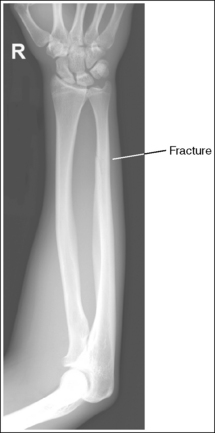

A fracture is located at the distal forearm. The wrist demonstrates a PA projection, whereas the elbow is in a lateral projection.

Because the joint closer to the fracture is in the true projection, no repositioning movement is needed.